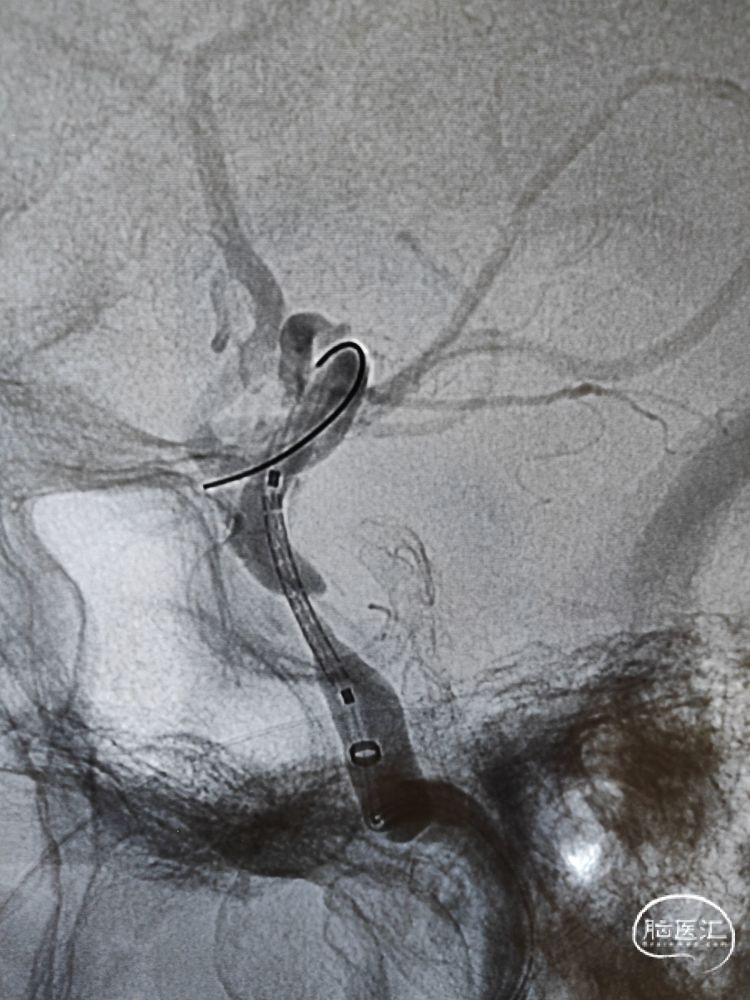

麻醉成功后,患者平卧位,双侧腹股沟区常规消毒、铺巾,取右侧腹股沟韧带中点下2cm处股动脉为穿刺点,采用Seldinger法穿刺成功,利用置换导丝置入8F鞘。选择侧位工作角度,在8F导引导管支撑下,将6F 115cm颅内支撑导管输送至海绵窦段接近狭窄近端建立稳定通路,大单弯塑形的0.014inch 200cm微导丝顺利通过狭窄段,换成正位工作角度将微导丝安全置于大脑中动脉M2段粗大分支平直段。

支架到位及释放:

在颅内支撑导管的支持下,沿微导丝将4.0mm*13mm Bridge椎动脉雷帕霉素靶向洗脱支架送至狭窄部位,支架到位比较顺利,通过狭窄处支架略有卡顿、微导丝有些回退,支架近端定位在接近正常段管径4mm处,略高于额定压扩张球囊释放支架,球囊缓慢泄张后造影提示支架内血流通畅,支架完全张开贴壁,局部无残留狭窄。